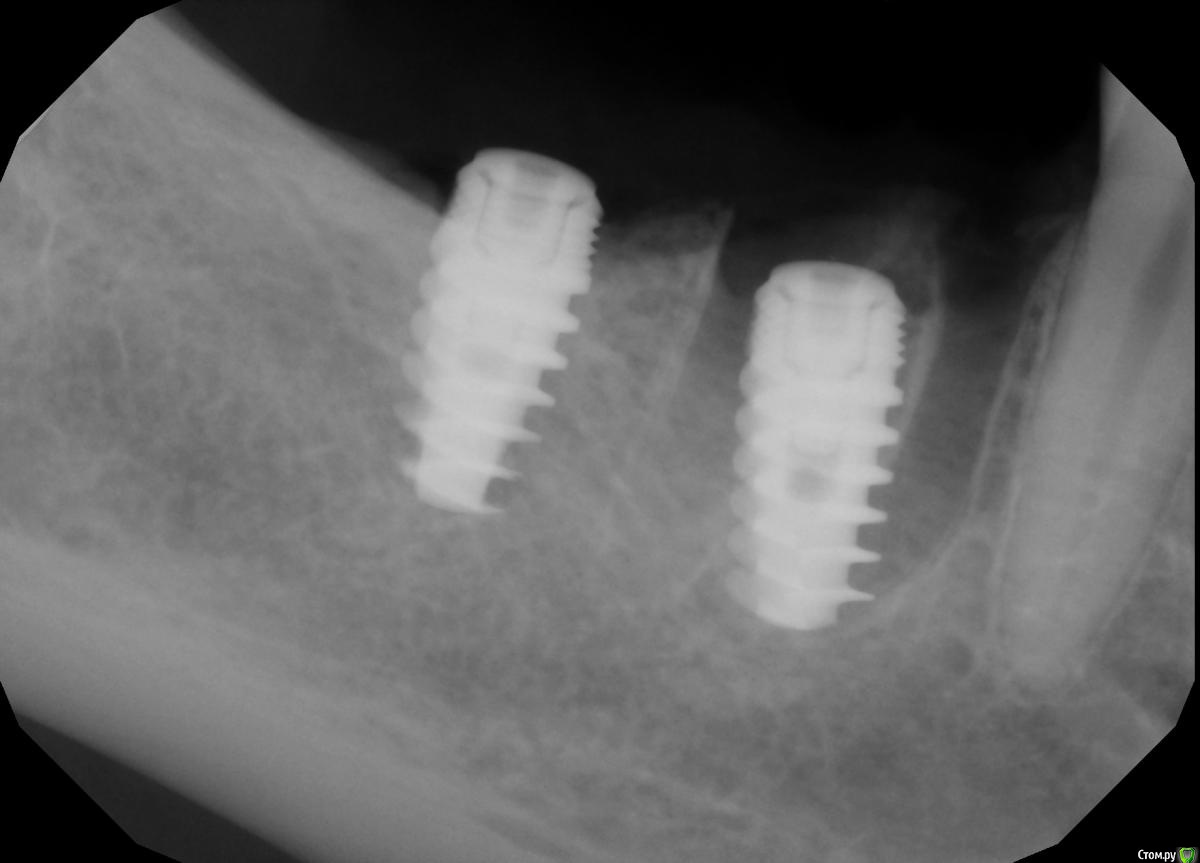

Demerchyan26 Опубликовано 3 марта, 2016 Поделиться Опубликовано 3 марта, 2016 Решил показать свой небольшой эксперемент. Ничего необычного, сложное удаление 1 час + имплантация, только без графта, лишь сгусток и торк меньше 5, не мог заглушку прикрутить. Открывал через 3,5 - 4 месяца. Система бюджетная - SGS, 7-ку немного не докрутил))) Ссылка на комментарий

red_butler Опубликовано 3 марта, 2016 Поделиться Опубликовано 3 марта, 2016 Возможно, но это не первая моя операция без графта, но первая, когда перегородки почти не осталось и торк получился минимальный, имплант слишком широкий взял.Проблема не в ширине, нужен был более длинный винт. А вот то что дистальный не досадили, это косяк, кость еще уйдет. Что с мягкими тканями? Ссылка на комментарий

diesel87 Опубликовано 3 марта, 2016 Поделиться Опубликовано 3 марта, 2016 При наличии ксено графта он будет каркасом для кортикалки, предохраняя ее от чрезмерной резорбции, пока в его пространства прорастают свежие сосуды и образуется молодая кость. На сгустке будет тоже хорошо, но с более выраженной резорбцией, но какая нам разница, имплант же там уже стоит, а вот с мягкими тканями считаю надо усиленнее работать в такой ситуации. Ссылка на комментарий